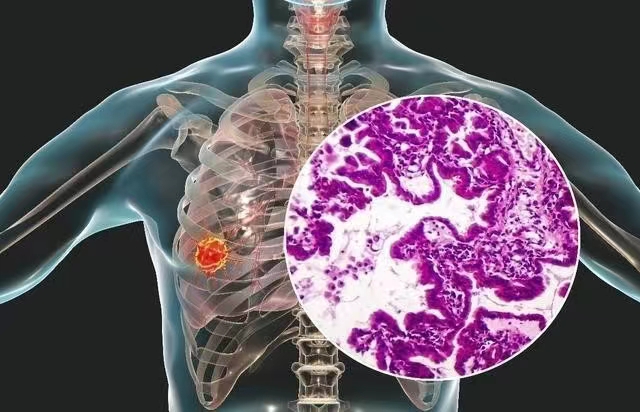

影像表现:右肺下叶前基底段胸膜下可见实性结节影,可见浅分叶,边缘局部略模糊,无毛刺及胸膜凹陷。

免疫组化:60305-1:CK7(+) ,TTF-1(-) ,NapsinA(-), P40(-) ,P53(野生型),Ki67(+约3%),CD68(组织细胞+)

病理诊断:(右肺下叶)粘液腺癌,未侵及胸膜,未见脉管浸润及气道播散,第7、9、10、11日淋巴结未见转移(0/2、0/1、0/2、0/3)。

原发性肺黏液腺癌,是特殊类型的一种腺癌,又称胶样腺癌,占肺癌的 0. 25% ,为少见的病理类型。

原发性肺黏液腺癌肿瘤细胞沿肺泡壁匍行生长,因起源于具有分泌黏液功能的杯状细胞或柱状上皮细胞,癌细胞产生的黏液在胞外形成黏液湖,表面有癌细胞漂浮,反映在 CT 图像上密度偏低,呈现为水样密度至软组织之间密度影。

原发性肺黏液腺癌影像学表现呈多样性,在 CT 形态学上可分为孤立病变型和弥漫型。(王兆宇老师认为孤立结节是病灶发展的一个时期)

CT表现主要表现为两种:一种是病变分布在肺野周围,边界不清的实性结节,此种结节、肿块型(孤立型)肺黏液腺癌更易出现假空洞征或囊变表现,CT 征象病理基础为肿瘤细胞沿管壁浸润性生长,管腔阻塞,形成活瓣,气体易进难出,并分泌液体所致。另一部分表现为伴支气管充气征,磨玻璃密度影或实变影,类似于炎症表现,此种磨玻璃影病变的病理基础可能是因为部分黏液被肿瘤细胞替代,间质增厚,而肺泡间隙未被填充充分,磨玻璃密度的边界可以因小叶间隔限制而边界清楚,也可以是不清楚的。裹挟有肿瘤细胞的粘液可以沿气道播散至远处肺泡(气道转移),这时期患者预后不好,可能与早期难以诊断、治疗不及时有关。